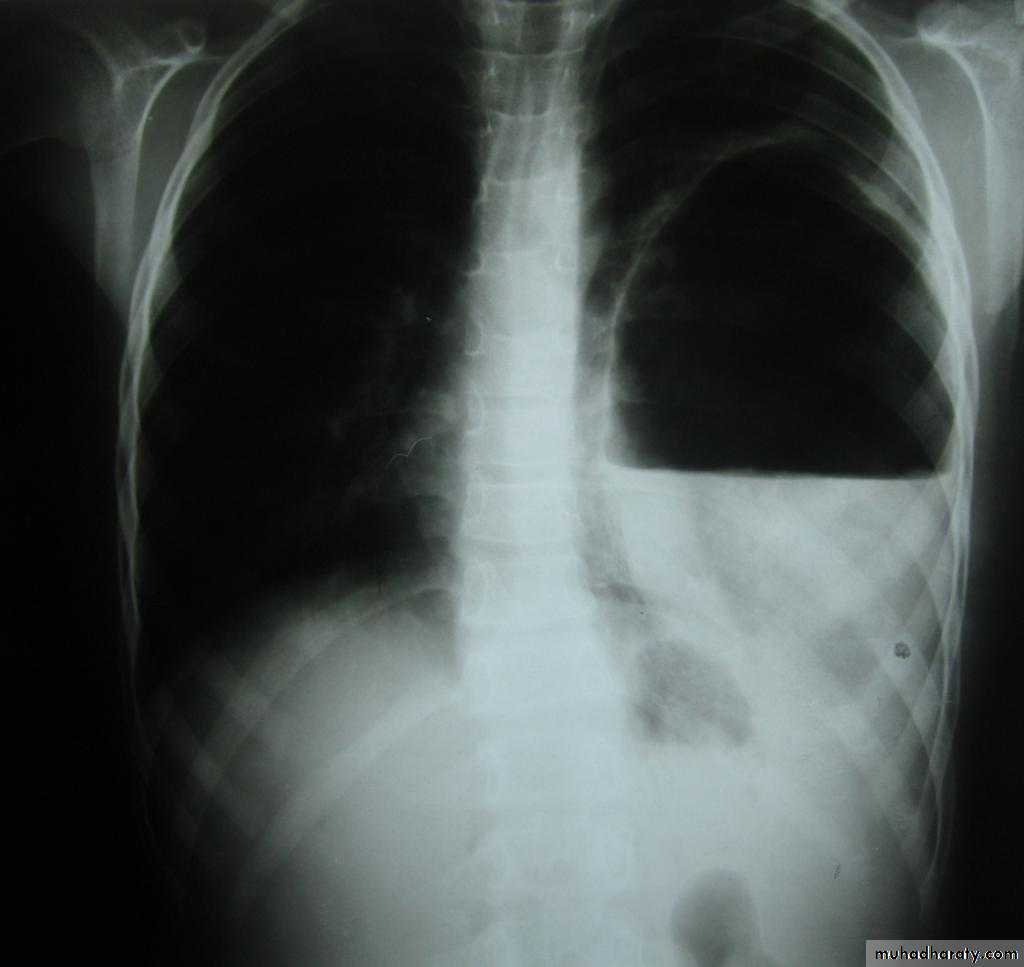

X-ray tension pneumothorax

Pneumothorax